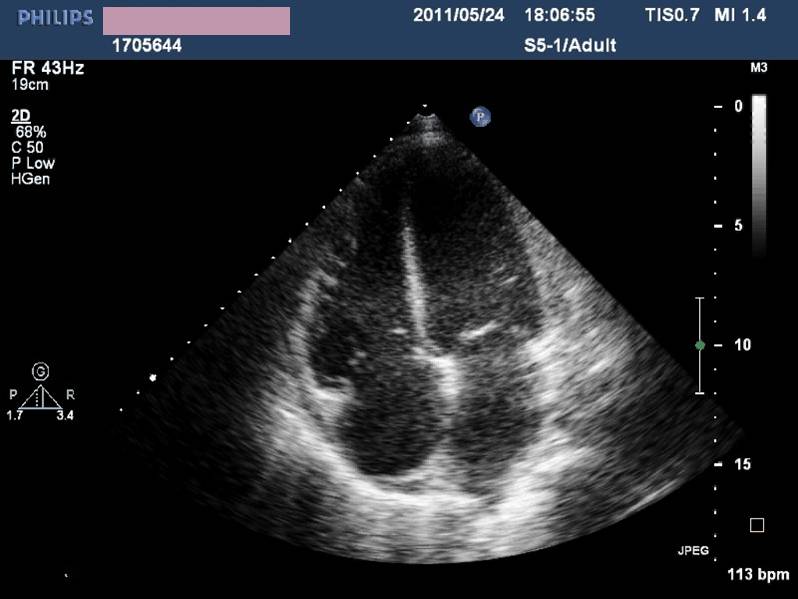

——床旁超声心动:节段性室壁运动异常,左房增大,轻度二尖瓣关闭不全,左室收缩功能减低,LVEF 45%,少量心包积液

现病史-超声心动

急性左心收缩功能不全